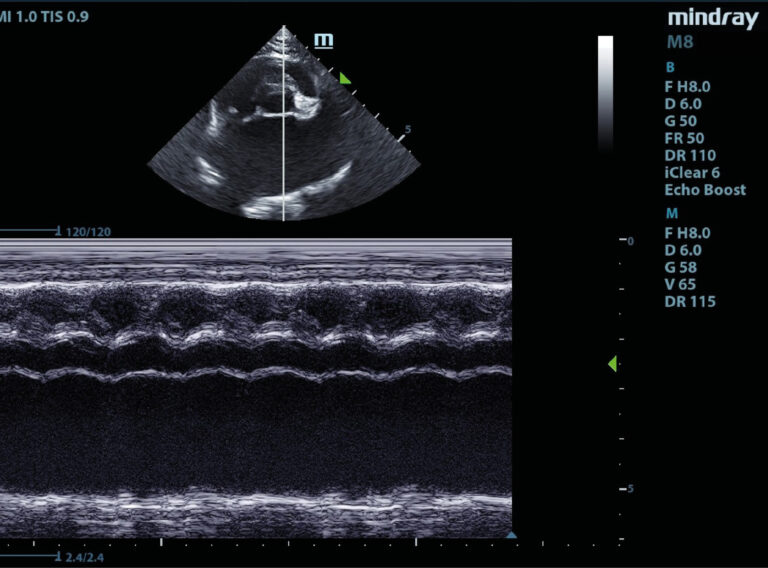

Bulldog francés, macho, de 9 años, asintomático. Acude a consulta para chequeo geriátrico rutinario.